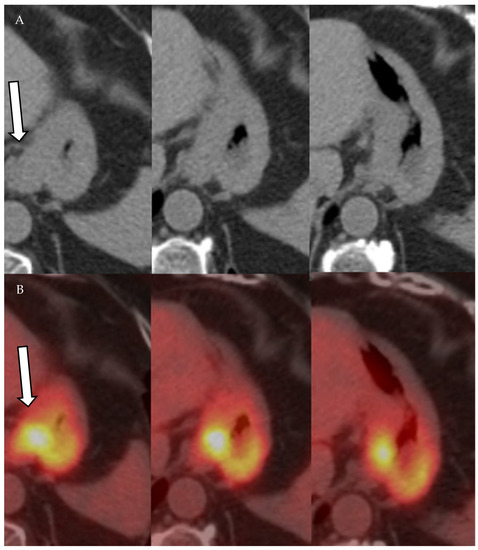

4.1.3. Positron Emission Tomography (PET) and Positron Emission Tomography-Computed Tomography (PET-CT)

- Mittra, E.; Quon, A. Positron Emission Tomography/Computed Tomography: The Current Technology and Applications. Radiol. Clin. N. Am. 2009, 47, 147–160. [Google Scholar] [CrossRef]

- Vallabhajosula, S. 18F-Labeled Positron Emission Tomographic Radiopharmaceuticals in Oncology: An Overview of Radiochemistry and Mechanisms of Tumor Localization. Semin. Nucl. Med. 2007, 37, 400–419. [Google Scholar] [CrossRef] [PubMed]

- Liu, B.; Gao, S.; Li, S. A Comprehensive Comparison of CT, MRI, Positron Emission Tomography or Positron Emission Tomogra-phy/CT, and Diffusion Weighted Imaging-MRI for Detecting the Lymph Nodes Metastases in Patients with Cervical Cancer: A Me-ta-Analysis Based on 67 Studies. Gynecol. Obstet. Investig. 2017, 82, 209–222. [Google Scholar] [CrossRef] [PubMed]

- Choi, H.J.; Ju, W.; Myung, S.-K.; Kim, Y. Diagnostic performance of computer tomography, magnetic resonance imaging, and positron emission tomography or positron emission tomography/computer tomography for detection of metastatic lymph nodes in patients with cervical cancer: Meta-analysis. Cancer Sci. 2010, 101, 1471–1479. [Google Scholar] [CrossRef]

- Riegger, C.; Koeninger, A.; Hartung, V.; Otterbach, F.; Kimmig, R.; Forsting, M.; Bockisch, A.; Antoch, G.; Heusner, T.A. Comparison of the Diagnostic Value of FDG-PET/CT and Axillary Ultrasound for the Detection of Lymph Node Metastases in Breast Cancer Patients. Acta Radiol. 2012, 53, 1092–1098. [Google Scholar] [CrossRef] [PubMed]

- Cochet, A.; Dygai-Cochet, I.; Riedinger, J.-M.; Humbert, O.; Berriolo-Riedinger, A.; Toubeau, M.; Guiu, S.; Coutant, C.; Coudert, B.; Fumoleau, P.; et al. 18F-FDG PET/CT provides powerful prognostic stratification in the primary staging of large breast cancer when compared with conventional explorations. Eur. J. Nucl. Med. Mol. Imaging 2014, 41, 428–437. [Google Scholar] [CrossRef]